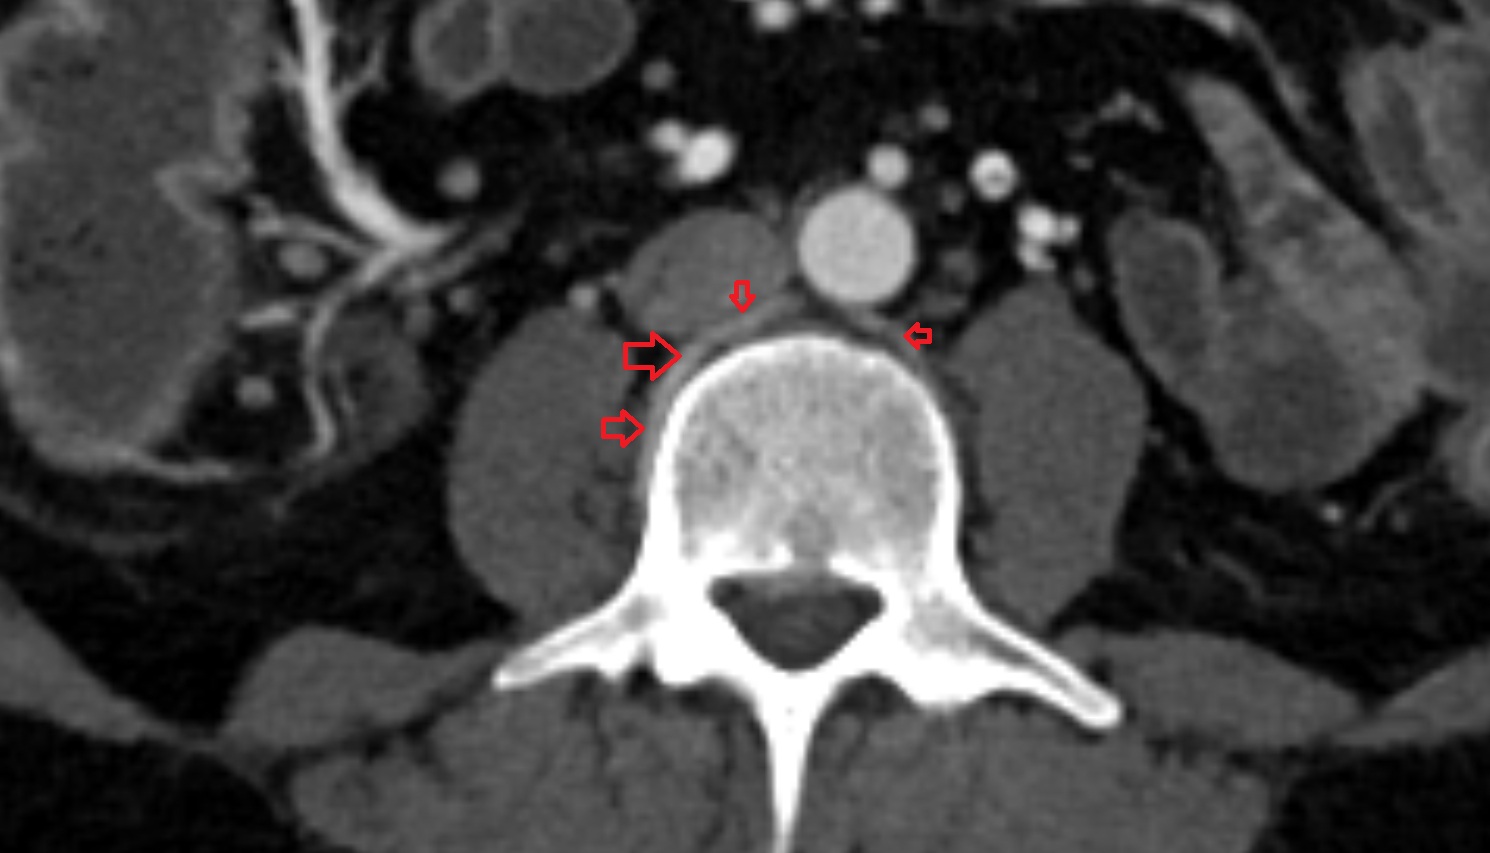

- Abdominal aorta

- Aortic bifurcation

- common iliac artery